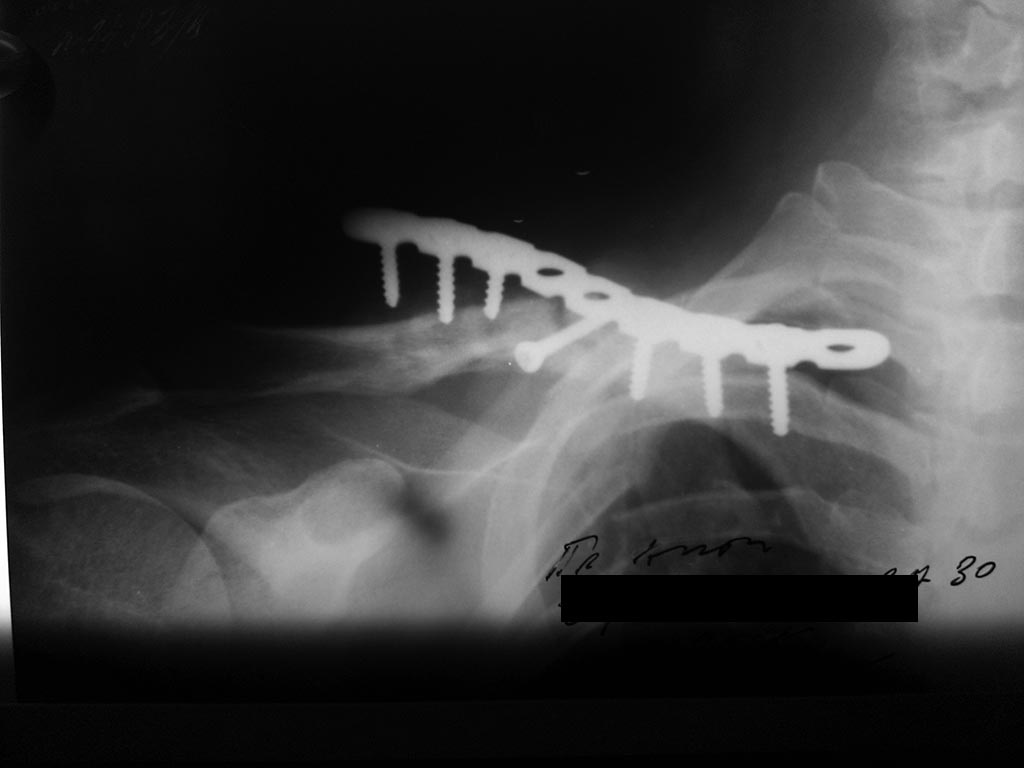

[Ortho] Последствия перелома ключицы

Пациент, 30 лет оперирован пластиной и винтами

Перелом на момент операции свежий, время операции - начало февраля 2015.

Через 1,5 мес на контрольном снимке стояние пластины удовлетворительное.

Еще через месяц - диастаз дистального конца пластины и дистального

отломка. Важно: больной не соблюдал режим, через 2 недели от момента

операции начал движения рукой.

Вопрос: Это рефрактура (как пишут рентгенологи)? Это несросшийся

перелом? Делать ли костную пластику? Спасибо!!!